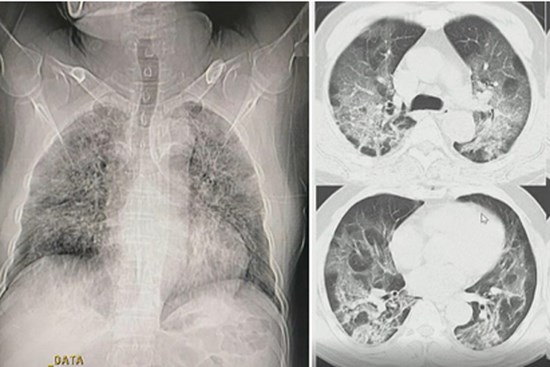

Hình ảnh phổi người mắc Covid-19 ở Việt Nam

Khi chưa xét nghiệm rRT-PCR hoặc kết quả âm tính, bác sĩ vẫn có thể kết luận bệnh nhân mắc Covid-19 dựa vào những tổn thương ở phổi.

Bệnh nhân ở Hải Dương tổn thương phổi rất nặng

BN867 tổn thương phổi lan tỏa hai bên và tiên lượng nặng nếu kèm bệnh nền.